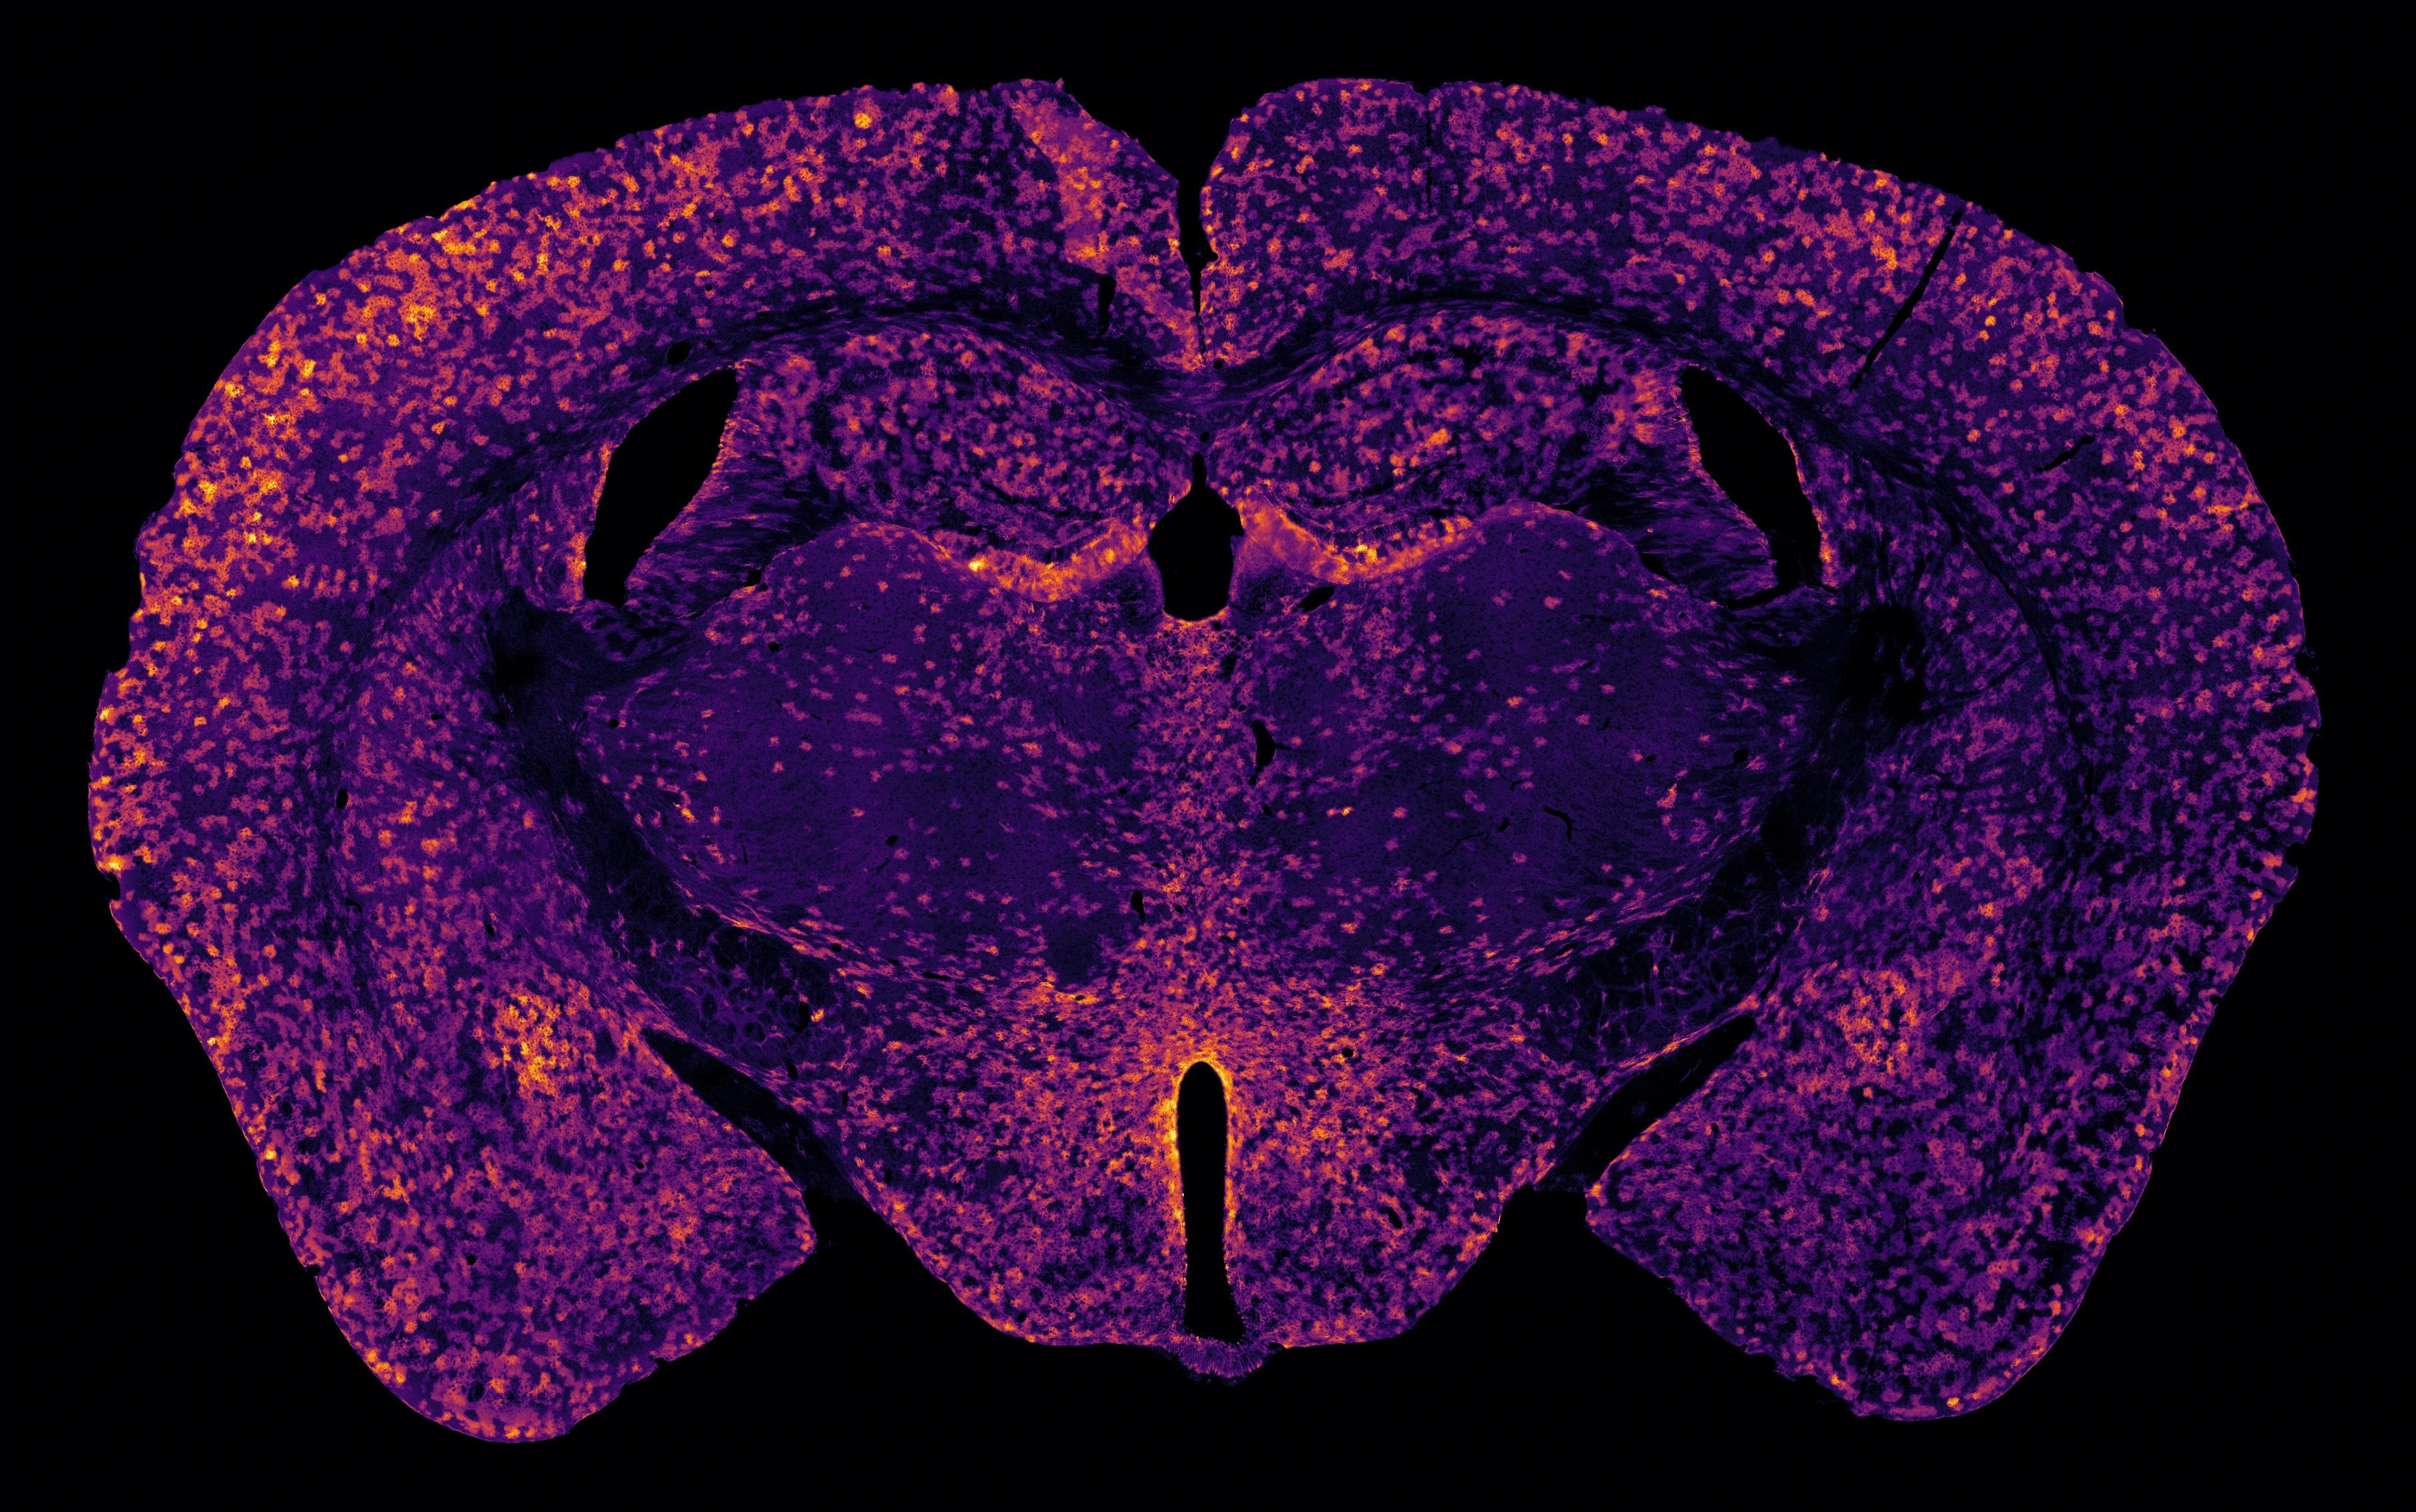

Confocal microscopy image of a mouse brain